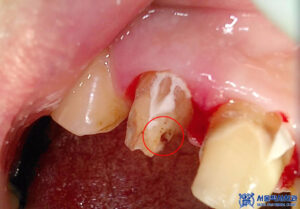

제거를 하고 확인해 보니,

내부로 충치가 생긴 것을

확인할 수 있었습니다.

이로 인해 불편감을

느끼고 계셨을 것으로

예상하였습니다.

본원에서는 충치가 있는 부분을

깨끗하게 제거하고,

신경치료를 진행하여

자연치아를 살리는 방향으로

계획을 수립하였습니다.